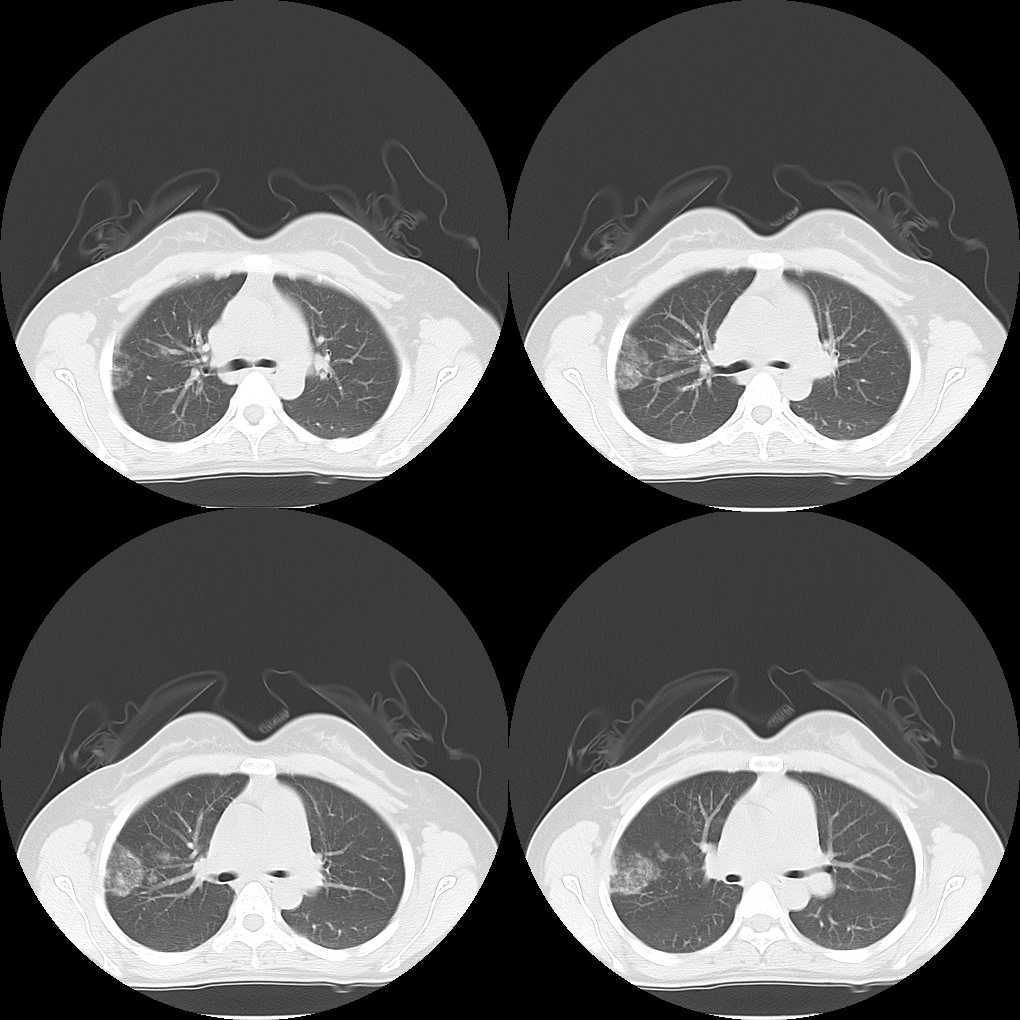

门诊拟 「 感染 」 抗炎治疗后 2 周复查

病灶较前有吸收,嗯,看来抗炎治疗是有效果的,而且也不咯血了;

完美!!